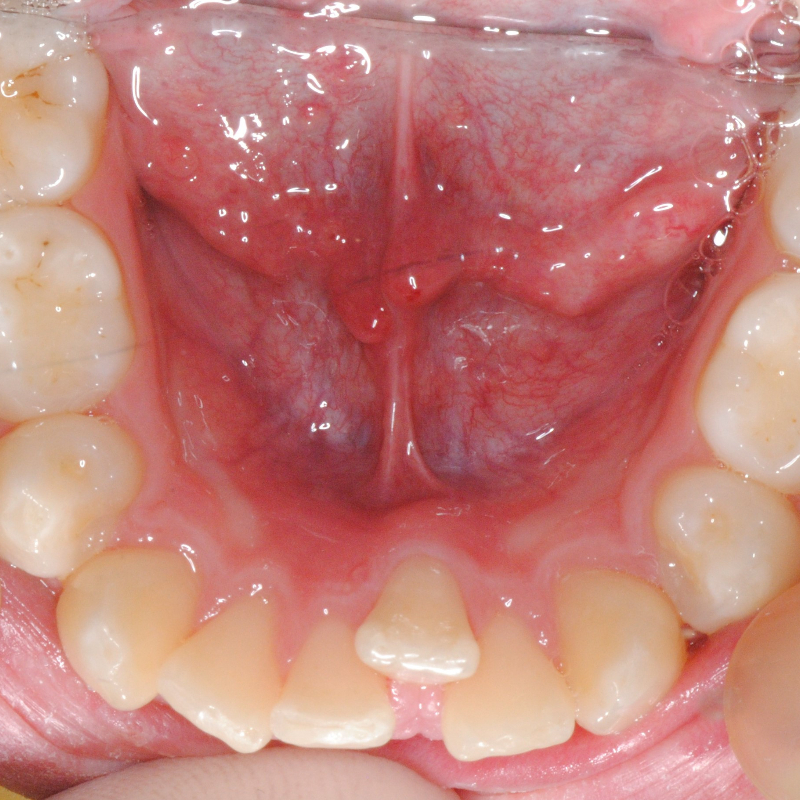

Prima e dopo trattamento con ortodonzia invisibile per l’allineamento dei denti